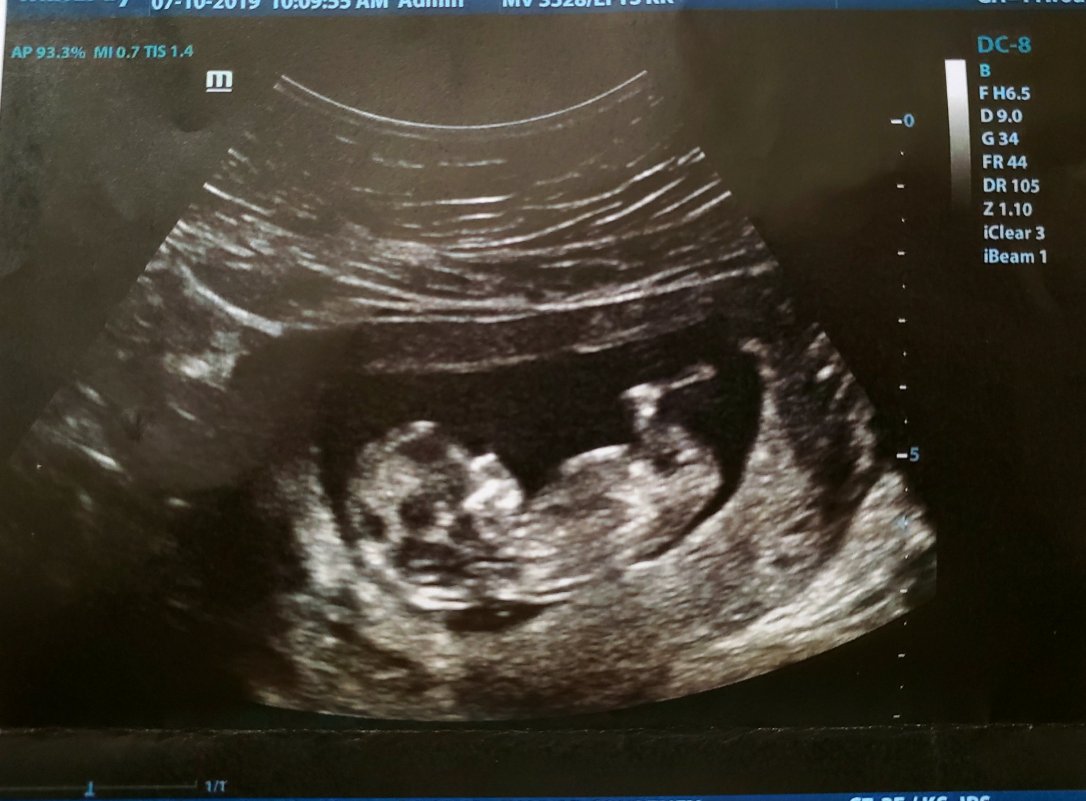

But let’s #tbt to last week; here’s baby’s most recent glamour shot:

The 12-week ultrasound was loooong. Like, an hour long. Baby has to be in a very specific position for them to get just as specific measurements. This is all part of the screening tests.

The ultrasound techs had to poke and prod all over my abdomen to coax the little nugget to move where they needed.

They eventually got what they needed, and I got to see baby’s right and left brain, stomach, spine, arms and legs.